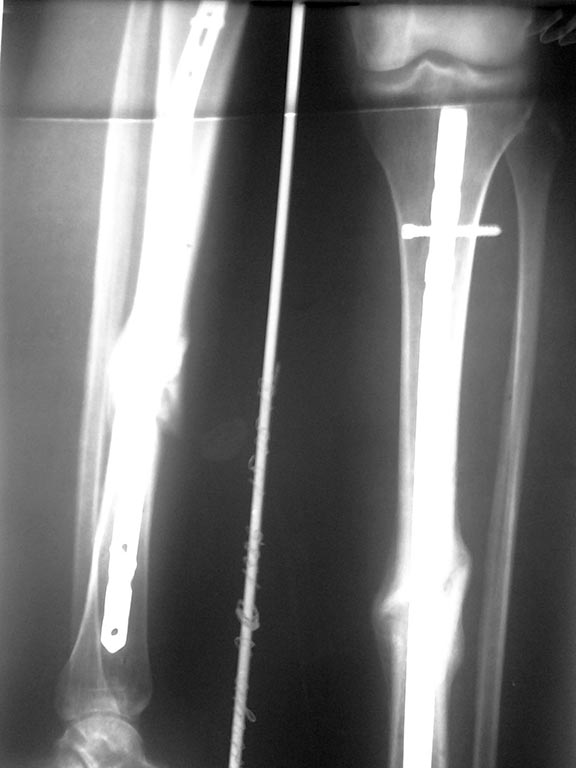

Re: ложный сустав б/берцовой кости на БИОС

Единственное, что стоило бы сделать - это снимки хорошего качества. Очень вероятно, что там увиденное можно будет трактовать как сращение.

Здравствуйте! Присоединяюсь к мнению Александра Челнокова. ИМХО: на рентгене - перифокальная костная мозоль. Думаю, что нужно оставить всё, как есть и продолжить нагружать конечность. А если всем после БИОС рубить малоберцовые кости (т.к. они срастаются задолго до момента динамизации стержня), то, что тогда получится? Спасибо.

общаяя картинка, выложенная щель между отломками прослеживается на протяжении всего периода сращения.

есть прицельно сфотографированный участок перелома

ничего делать не надо, прицельный снимок это только подтверждает

Перелом сросся!

другая проекция прицельного снимка, на мои сомнения направлена стрелка

Присоединяюсь к выше сказанному: перелом сросся. И ВСЕ!!! снимки показывают на консолидацию.А процесс ремоделирования может занять несколько лет, если уж действительно сомневаетесь, сделайте рентгенконтроль через пару месяцев, сравните динамику, я думаю результат Вас удовлетворит.

Если есть сомнения, то выполните динамизацию стержня, а полное удаление конструкций отложите на несколько месяцев.